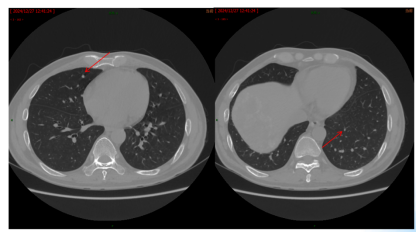

影像学检查:2024年7月30日,院外腹部CT显示乙状结肠管壁增厚,考虑肿瘤性病变(cT3N2,图1),2024年8月5日,肝脏MRI显示肝脏多发转移灶(侵犯门静脉右支、肝右静脉,图2)。2024年8月2日胸部CT显示双肺结节待排(图3)。

CEA、CA19-9略微升高(图17),肝脏多发转移瘤较前增多、增大(图15/16),双肺结节较前增多、增大(图14),评估为PD。

图14. 2025年2月25日CT:双肺结节,较2024年12月27日CT增多、增大

图15. 2025年2月25日MRI:肝脏多发转移瘤,较2024年12月29日MRI增多、增大

图16. 2025年2月25日MRI:术区未见异常强化影